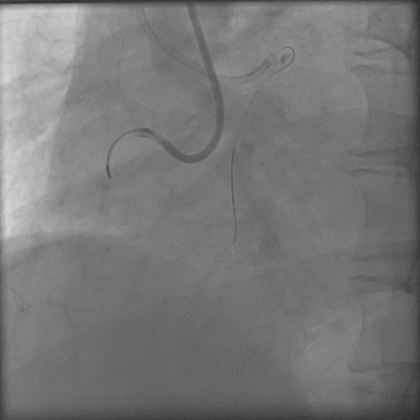

预案正向找到血管结构,ADR术式可快速高效开通右冠CTO,即使走逆向,也得进行充分正向准备,以进行Reverse-Cart;选择7F-AL1强支撑指引导管,由于近端纤维帽坚硬, Gaia3导丝、P200导丝前向试探失败;XTA、P200导丝Knuckle失败;

导丝怎么扩秦川论剑|张勇:攻坚克难——解决器械难以通过的CTO病变之技术图谱_https://www.jmylbn.com_新闻资讯_第17张

导丝怎么扩秦川论剑|张勇:攻坚克难——解决器械难以通过的CTO病变之技术图谱_https://www.jmylbn.com_新闻资讯_第18张

Carlino后导丝仍无法前行;